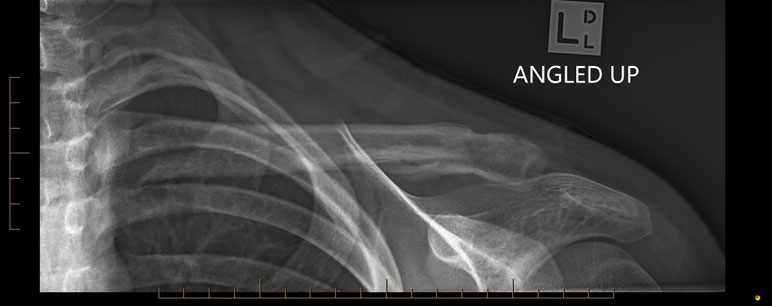

A 15 year old female fell from her pushbike causing a displaced left mid-shaft clavicular fracture. Seen 5 days later, plate & screws inserted 2 days later.

Image

DIsplaced fracture before surgery

DIsplaced fracture after surgery

Move the slider to compare before surgery and after surgery